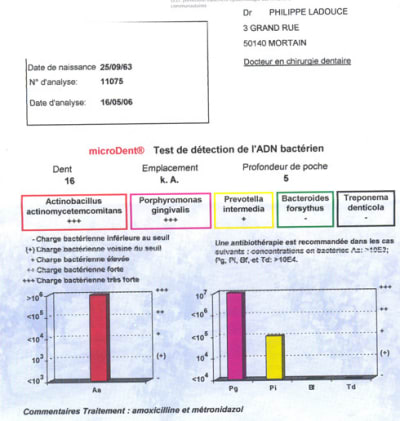

compte tenu de la discordance entre ce qui est constaté perte sevère et faible inflammation, du contrôle de plaque très bien réalisé et le présence de pus au niveau de 12....... après mise en route d’un contrôle de plaque adapté ( méthode de bass lingual + fluorure d’etain dentifrice et Bd b......PAS H202 + BICARB ) .....un test microbiologique est réalisé qui montre la présence de patho virulents.....( voir résultats)

l’atb améliore immédiatement la situation ....

1-pour une approche type Bonner grnd prescripteur de flagyl ( et pourtant pas d’amibes dans ce cas ) nous aurions eu toutes les chances d’avoir un pepin sur le moyen terme car Aa present au niveau de 16 est peu sensible à la molécule ....